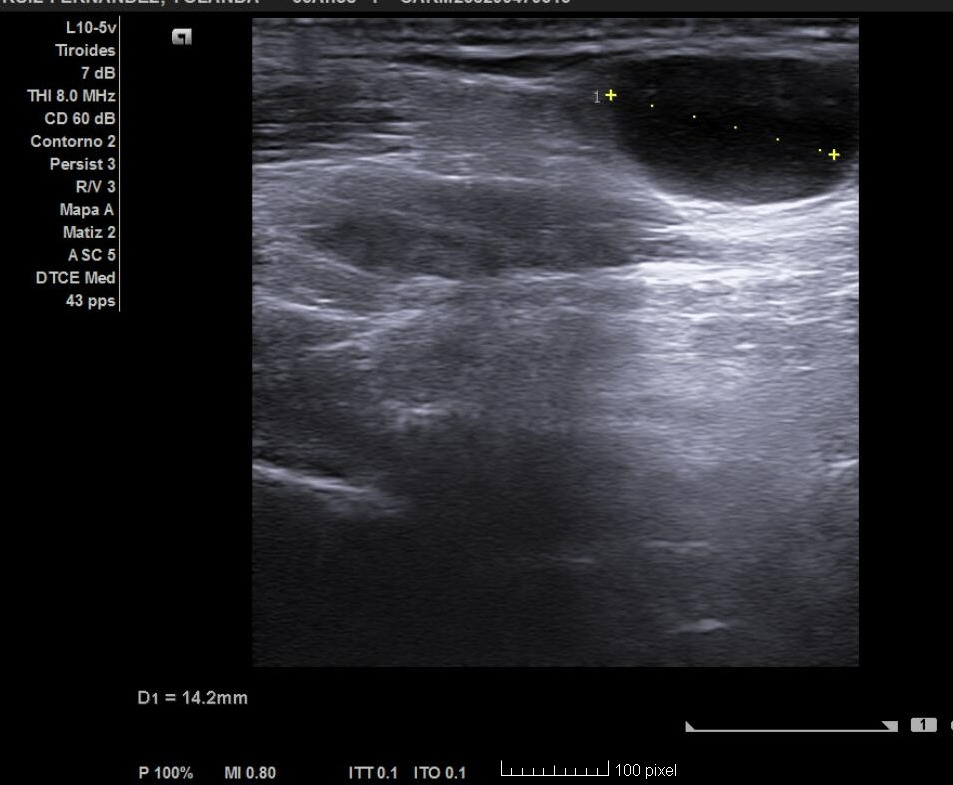

En la analítica se objetiva ligera leucopenia y neutropenia. Serología positiva para IgG frente a virus Epstein–Barr. Resto de parámetros normales, incluidas VSG y PCR. Tras 3 semanas se realiza nuevo control ecográfico, observándose cambios respecto al estudio previo: agrandamiento de adenopatías mayores de 10 mm, hipoecogénicas, en conglomerado, con pérdida del hilio y aparición de una adenopatía supraclavicular derecha de 14 mm con vascularización periférica. Estos hallazgos resultan sugestivos de proceso linfoproliferativo, por lo que se tramita derivación preferente a Hematología con solicitud de PAAF, que se realiza en 48 horas. Tras su valoración, la paciente ingresa para completar estudio.

La ecografía en Atención Primaria permite identificar signos ecográficos de alarma en adenopatías (cociente longitud/anchura > 1,3, redondeamiento, ausencia de hilio, alteración cortical, vascularización periférica o aberrante). Su uso agiliza el diagnóstico, optimiza recursos y mejora la capacidad resolutiva. En este caso fue determinante para sospechar patología maligna y priorizar el estudio hematológico, facilitando un abordaje precoz y multidisciplinar.